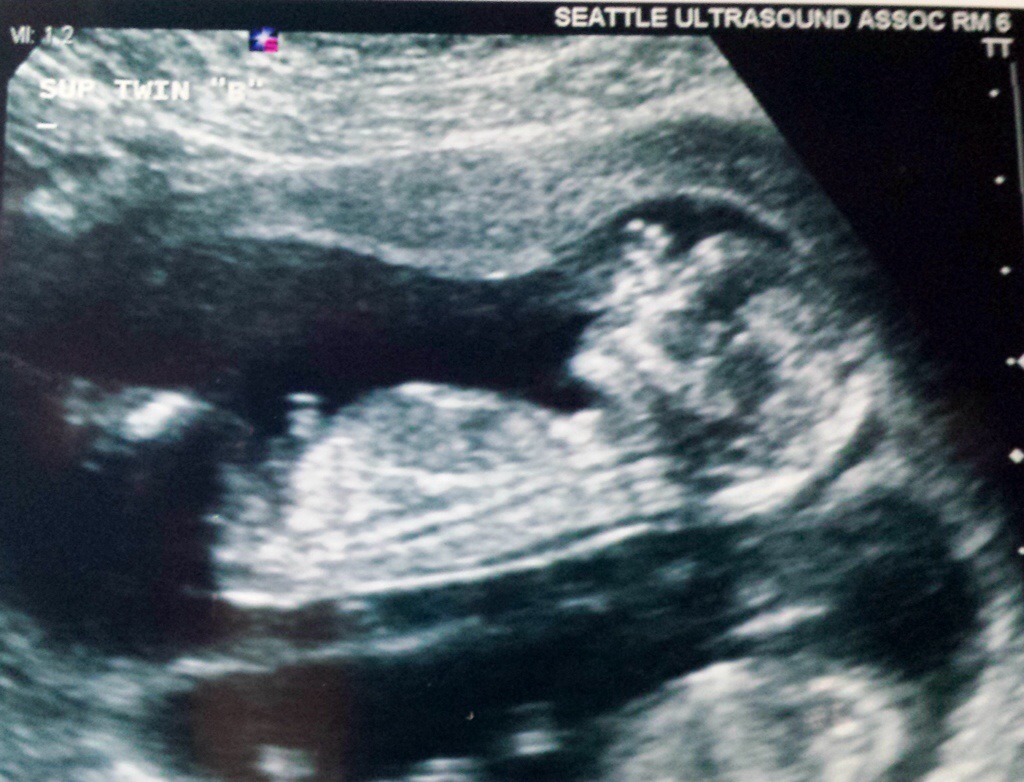

Baby B

Baby A & B, Ultrasound tech said this will be the last time we’ll be able to see them together in the same image, they will be getting too big soon.